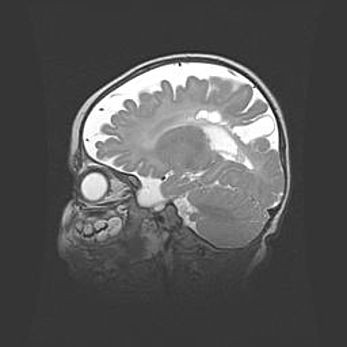

Мальформация Денди-Уокера. Киста задней черепной ямки.

Агенезия мозолистого тела.

Возраст: 2,5 месяца

Вес: 2420 г

Пол: женский

Окружность головы: 37 см

Срок гестации: 32 недели

Мальформация Денди—Уокера — редкий вид патологии ЦНС, представляющий собой врожденный порок развития каудального отдела ствола и червя мозжечка, ведущий к неполному раскрытию срединной (Мажанди) и латеральных (Лушка) апертур IV желудочка мозга. Для этогно синдрома характерна триада симптомов: гипотрофия червя мозжечка и/или полушарий мозжечка, кисты задней черепной ямки, гидроцефалия различной степени. В 70% случаев порок сочетается и с другими аномалиями головного мозга, в частности с агенезией мозолистого тела.